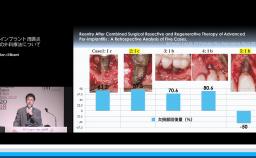

本講演では,上顎洞底挙上術の一手法である側方開窓術の術前臨床的判断基準,術式詳細,臨床経過,CBCT所見,術後偶発症,文献的考察から,開窓部へのバリアメンブレン設置を整理する.

上顎洞底挙上術(術式や合併症など)の理論が理解できる。